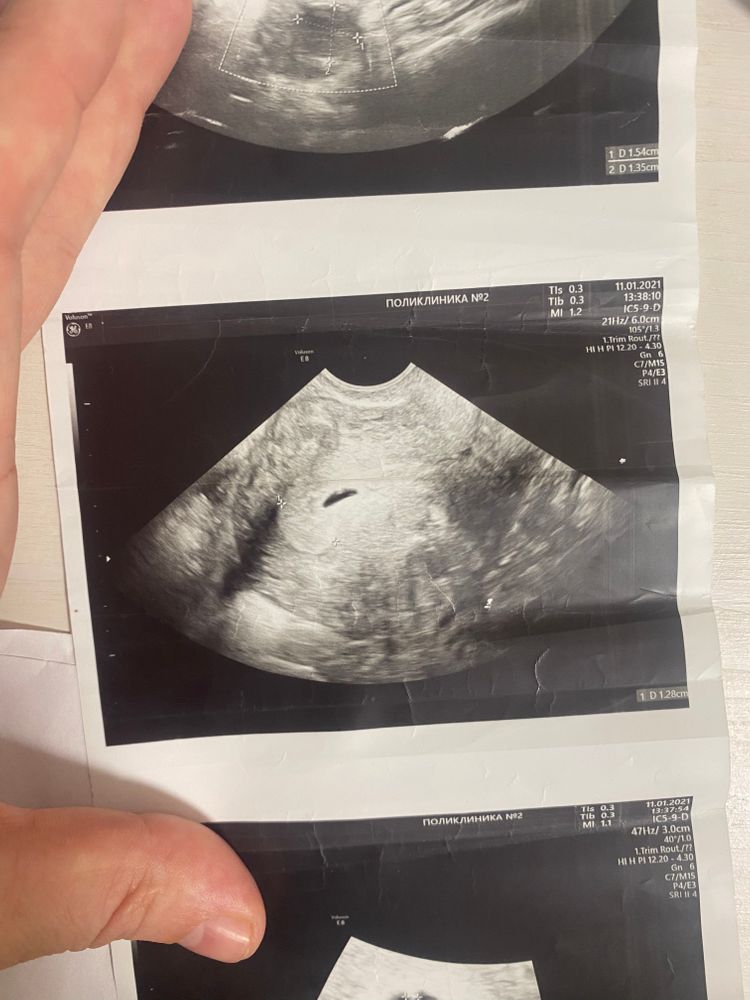

Валерия, это мое узи на 14 дпп, хгч был больше 2 тыс. Через 7 дней плодное яйцо было круглой формы. Просто могло быть локальное напряжение миометрия на введение датчика узи. Конечно надо поберечься, но переживать сильно тоже не стоит.

Ирина, какое чёткое узи 😅 мой снимок просто жалкое подобие узи какое-то 😅😅😅